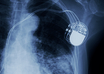

Artificial intelligence could select heart failure patients for expensive treatment